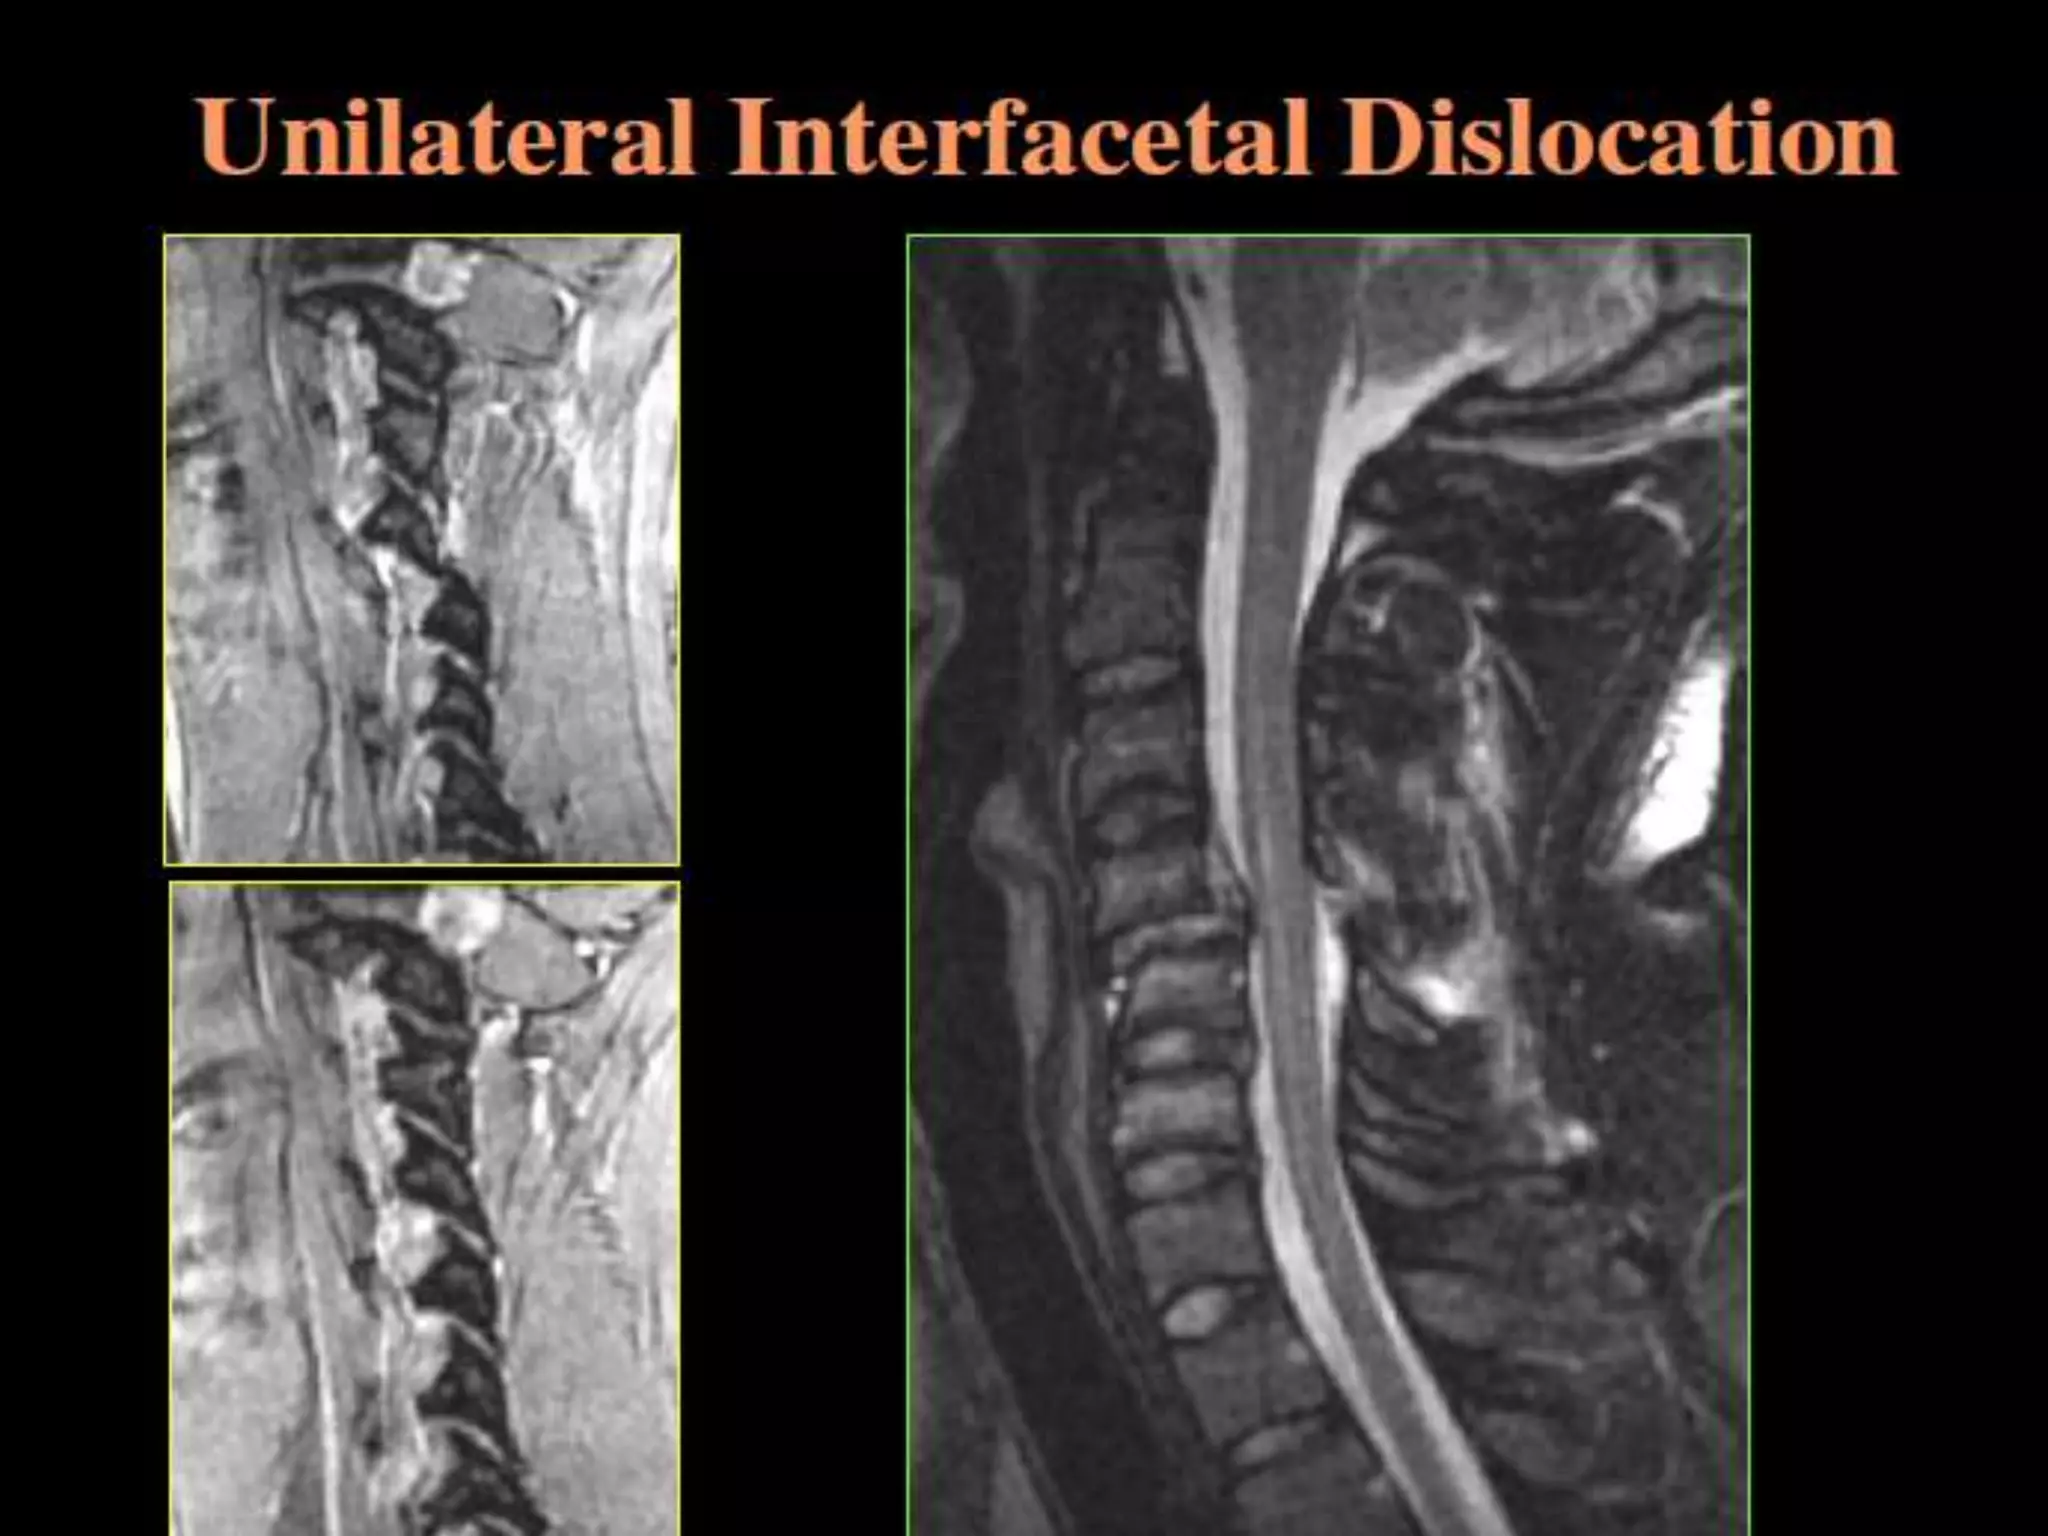

1. Unilateral Interfacetal Dislocation:

– Dislocation of facet joint opposite that of the

direction of rotation.

– Posterior ligament complex and articular

joint capsule are disrupted.

– ALL, disc and PLL intact.

– Most common at C5-6, C6-7.

– Impaction fractures tip of either articular

mass (up to 70%).

– STABLE, unless FX isolates articular process.

Hyperflexion Injury withRotation. 1. Unilateral Interfacetal Dislocation: – Dislocation of facet joint opposite that of the direction of rotation. – Posterior ligament complex and articular joint capsule are disrupted. – ALL, disc and PLL intact. – Most common at C5-6, C6-7. – Impaction fractures tip of either articular mass (up to 70%). – STABLE, unless FX isolates articular process.